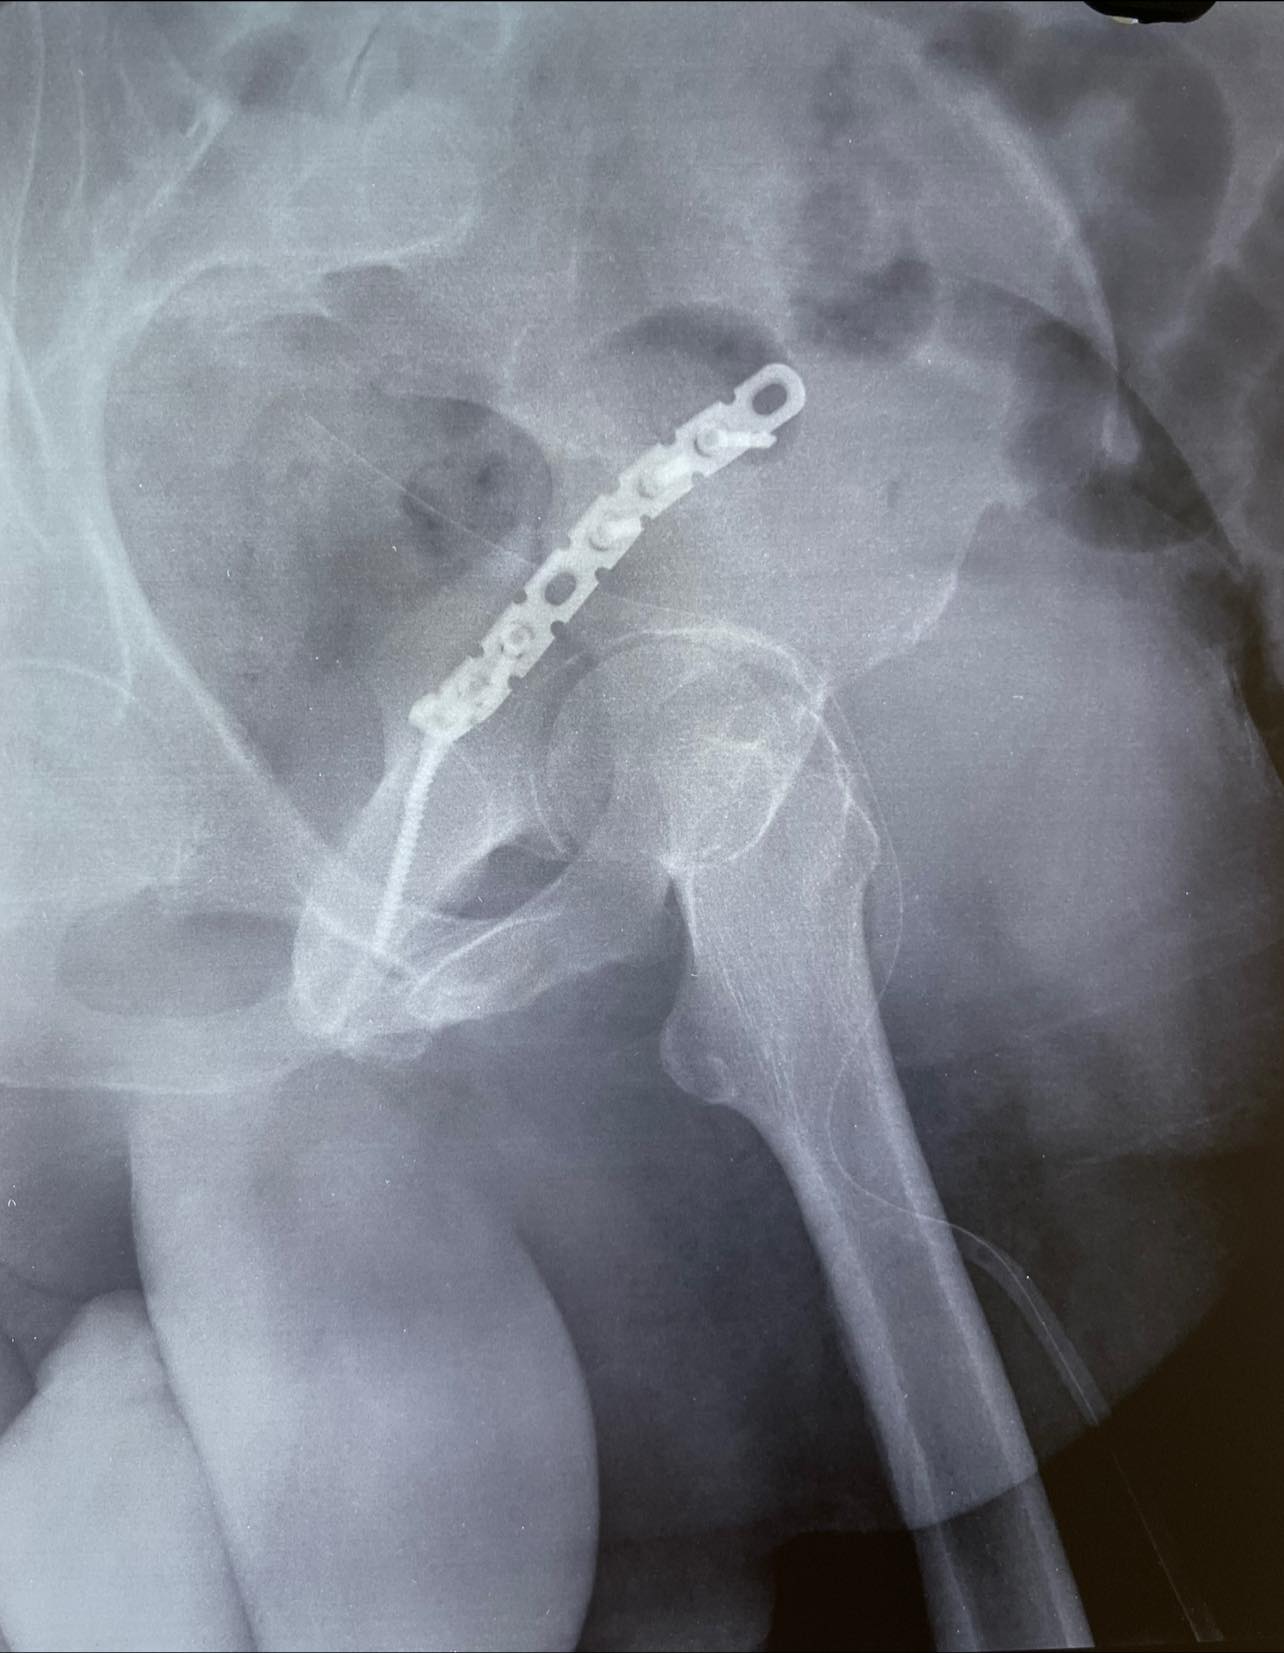

Considering the general condition and weight of the patient just fixing the posterior column felt like the right thing to do, the joint congruity is within the range of standard deviation.